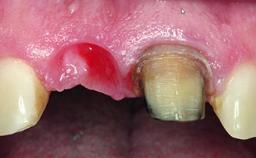

Replacement of an Ankylosed Upper Left Central Incisor: Bone Augmentation and Socket Grafting, Late Placement of an RC Bone Level Implant

A 15-year-old male patient was referred to us by his pediatric dentist in June 2004 for evaluation of treatment options for his failing tooth 21. The patient had recently seen an endodontist for internal bleaching and been advised that there had been significant resorption and ankylosis. The patient’s mother was concerned because the tooth appeared shorter than the adjacent one. His past dental history was significant for trauma (September 2001), where the tooth had been avulsed and reimplanted. Teeth 11 and 21 had been endodontically treated.

Bone Volume Deficient horizontally, requiring prior grafting